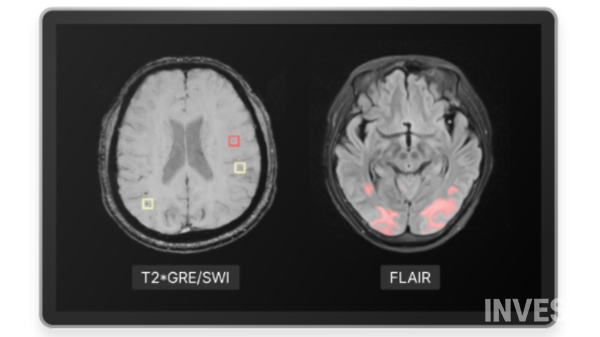

뉴로핏의 핵심 경쟁력은 자체 개발한 AI 기반 뇌 MRI 분할 기술 '세그엔진'(SegEngine)에 있다. 이 기술은 딥러닝 알고리즘을 통해 뇌 영역별 해부학적 특성을 학습시켜 기존 8시간 이상 소요되던 뇌 분할 과정을 1분 내로 단축시켰다. 더불어 15~20%에 달하던 기존 기술의 연산 실패율을 1.3%까지 대폭 낮추며 정확도를 크게 향상시켰다.

또 세그엔진은 1분 만에 97개 뇌 영역의 자동 구획화를 지원한다. 이를 바탕으로 회사는 △뉴로핏 아쿠아(AQUA) △뉴로핏 아쿠아 AD(AQUA AD) △뉴로핏 스케일 펫(SCALE PET) △뉴로핏 테스랩(tES LAB) △뉴로핏 잉크(innk) 등 다양한 제품 라인업을 구축했다.

이 중 '뉴로핏 아쿠아 AD'는 '뉴로핏 아쿠아'의 알츠하이머병 특화 버전으로, 항아밀로이드 알츠하이머병 치료제 투약 과정에서 필요한 모든 뇌영상 분석 기능을 제공한다. 치료제 투여 전 환자 적격성 평가부터 치료 중 부작용 모니터링, 투약 후 치료 효과 분석까지 종합적인 기능이 포함된다.

구체적으로 뉴로핏은 상장 자금 중 약 90%에 해당하는 247억 원을 연구개발에 집중 투자한다. 이 중 대부분은 핵심 제품인 뉴로핏 아쿠아, 뉴로핏 스케일 펫, 뉴로핏 아쿠아 AD의 고도화 작업에 사용된다. 특히 회사는 항아밀로이드 치료제 핵심 개발사를 통해 확보한 대규모 ARIA(아밀로이드 관련 영상 이상) 데이터셋을 활용해 제품의 검증과 고도화를 진행할 예정이다.